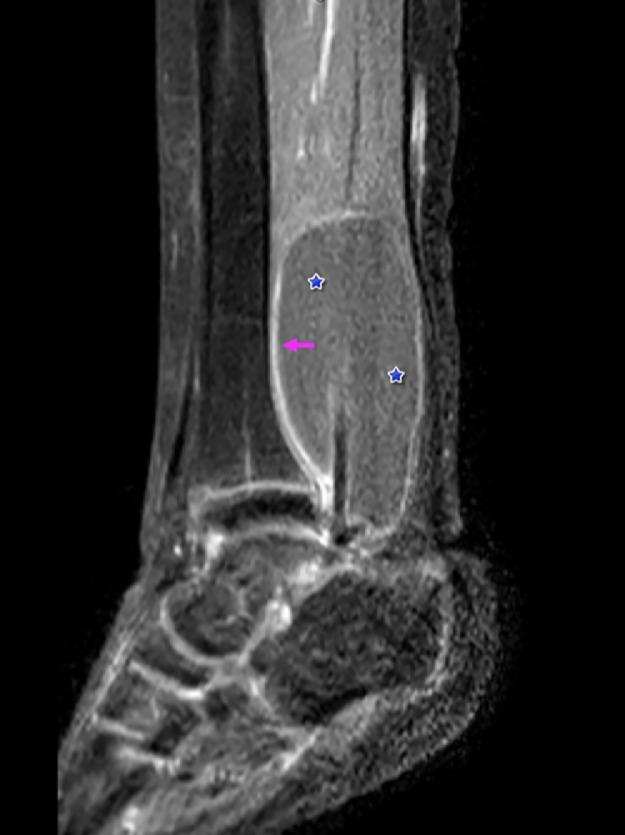

Pigmented villonodular synovitis is an uncommon benign neoplastic proliferation associated with the synovium, bursa, or tendon sheaths; most commonly occurring in the third to fourth decade of life. It is rare in children and may be painful or painless. Magnetic resonance imaging is the diagnostic study of choice. In this report, the radiologic, ultrasound, and magnetic resonance imaging findings of pigmented villonodular synovitis of the flexor hallucis longus in a 12-year-old girl are discussed. We briefly review the surgical findings as well. To our knowledge, this is the first case report that simultaneously synthesizes the imaging findings of 3 diagnostic imaging modalities for optimal visualization and is the youngest reported case of pigmented villonodular synovitis of the flexor hallucis longus tendon.

色素沉着绒毛结节性滑膜炎是一种罕见的与滑膜、滑囊或腱鞘相关的良性肿瘤性增生;最常发生于人生的第三个至第四个十年。在儿童中罕见,可能有疼痛或无痛。磁共振成像(MRI)是首选的诊断检查方法。在本报告中,讨论了一名12岁女孩拇长屈肌色素沉着绒毛结节性滑膜炎的放射学、超声和磁共振成像表现。我们也简要回顾了手术所见。据我们所知,这是第一例同时综合三种诊断成像方式的影像学表现以实现最佳可视化的病例报告,也是已报道的最年轻的拇长屈肌腱色素沉着绒毛结节性滑膜炎病例。